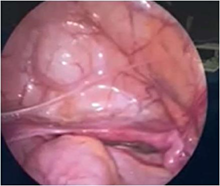

In our patient, exploratory laparoscopy was performed, which confirmed the presence of dysgenetic gonads. It was removed and histologically studied, which reported the presence of uterine tubes with fimbriae, without significant histological alterations. In both gonads, no tissue macroscopically compatible with the ovary was observed; microscopically, remains of ovarian parenchyma were observed, composed only of stroma and rete ovarii, without follicular structures or findings of malignancy (Figures 13).1–4

Figure 1 Note the presence of ectopic adrenal tissue in the gonad.